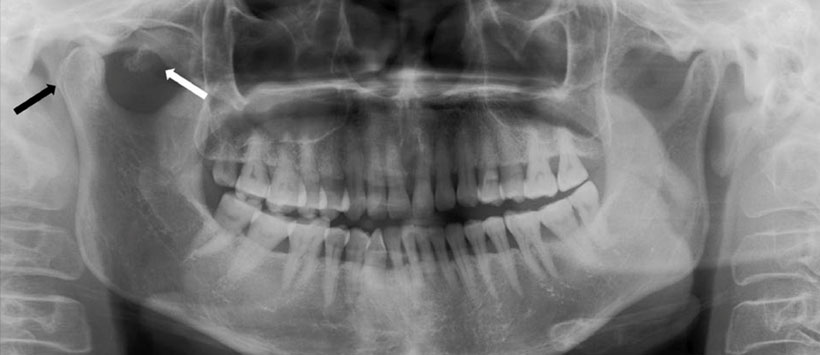

Caso 2: Mujer de 30 años con hinchazón del lado derecho que se había desarrollado en los últimos 6 meses. Hace un mes fue diagnosticada con artritis de ATM y se encuentra con medicación que no tuvo efecto positivo (Figura 4 y 5).

Figura 4: Radiografía panorámica que muestra cóndilo mandibular irregular con ensanchamiento del espacio articular del lado derecho.